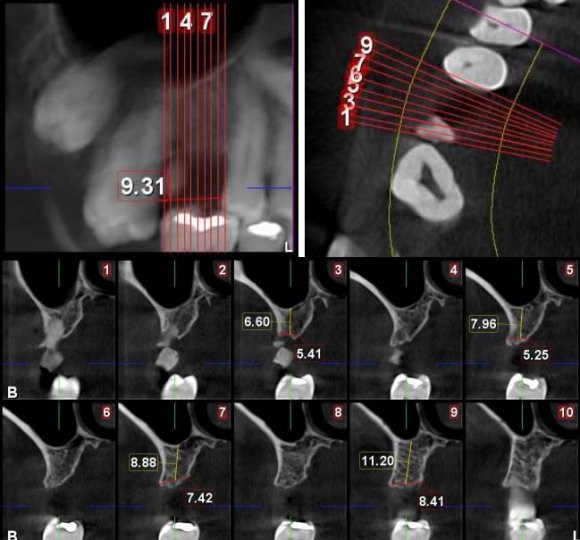

A 44-year male patient desired the replacement of a grossly decayed tooth in his upper right back teeth region. The CBCT revealed a reduced bone height of 8 mm (Figure 6). Minimal atraumatic extraction of the maxillary right first molarroot piece was performed before proceeding with the implant surgery. Then, the osteotomy was started with a 2.0 mm diameter twist drill from the CAS kit. It was used along with the stopper. It was then followed by the drills with increasing diameter upto 1 mm short of the sinus floor with a drilling speed of 800 rpm. Then, the 3.6 mm bur was used for the extension of the osteotomy, perforating the sinus floor. The integrity of the membrane was analyzed with the depth gauze while slightly lifting the membrane. Then, the hydraulic hoist was implanted and steadied into the drilled hole and the saline solution was injected. 3 mm sinus floor elevation is expected by using 0.30 mL solution. [7]It was then drowned out and injected again until the anticipated advancement was achieved. The xenograft was condensed with the help of the carrier and condenser. It was then followed by implant placement using the self-tapping method and the cover screw was placed (Figure 7), followed by adequate soft tissue closure. The patient was instructed with proper oral hygiene instructions and was recalled after 10 days for suture removal. A healing abutment was used to replace the cover screw after four months. And by the end of the 4 th month, the final prosthesis was delivered (Figure 8). The patient is being followed up for 1 and a half years now and has shown satisfactory results.